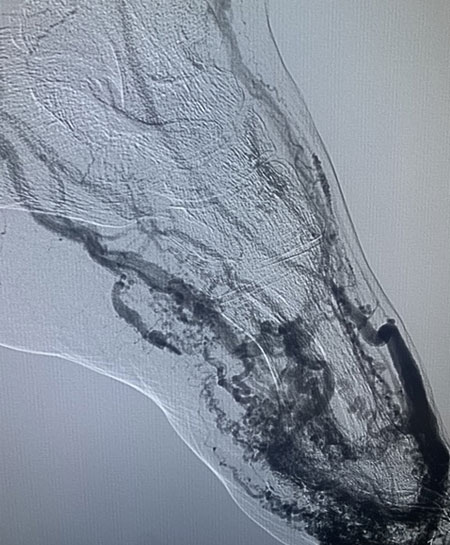

Αρτηριοφλεβικές αγγειοδυσπλασίες (AVMs) και Αρτηριοφλεβικές επικοινωνίες (AVF):

Εμβολισμός: Φραγή της ροής του αίματος προς τη δυσπλασία, μέσω ενδαγγειακών τεχνικών.